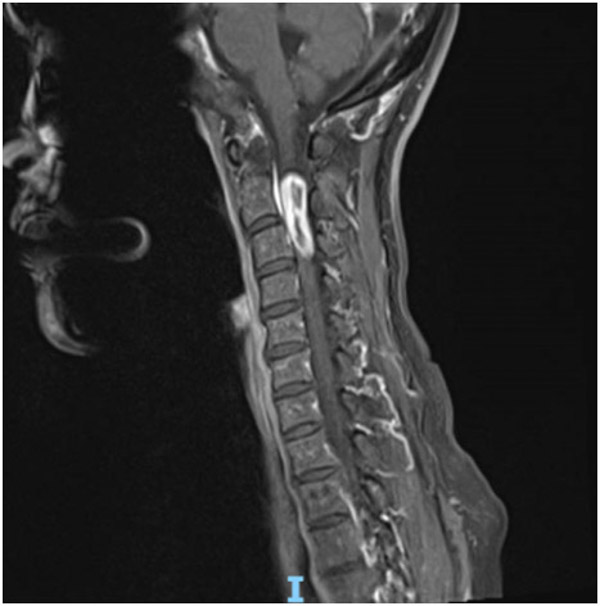

58岁的兰女士因胸部束缚感2年,左上肢麻痛1年在当地医院就诊,经检查发现患者高位颈髓区域有一颗巨大肿瘤,手术风险大,术后出现高位截瘫的可能性非常高。为求更好的治疗方案,兰女士辗转了多家医院,最终来到了柳州市人民医院神经外科。

了解到患者的病情后,神经外科治疗团队迅速作出了判断:此类肿瘤常规手术要采用至少15cm以上长切口切除,切除多节段椎板影响脊柱的稳定性,需要行内固定手术,颈1、2内固定将严重影响患者的颈部活动,为日后生活带来诸多不便。

于是神经外科治疗团队便针对患者的特点制定了手术方案,采用改良侧方肌间隙半椎板入路,仅需6cm手术切口,术中电生理监测在显微镜+神经内镜下全切肿瘤,这种方法可精准的暴露颈髓侧方及腹侧的肿瘤,避免颈髓的牵拉,减少了手术创伤,缩短手术时间,后路绝大部分椎板、肌肉及韧带保留,降低了患者术后椎柱失稳的风险,无需内固定。

听了医生的解释后,兰女士欣然决定进行手术治疗,困扰自己的2年多的病痛终于有了妥善的解决办法。手术非常成功,术后症状便得到了缓解,2周后患者痊愈出院,目前颈部活动自如,无任何后遗症。